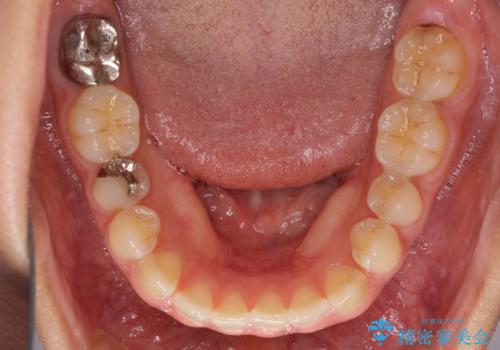

下の前歯が上の前歯を突き上げるように咬合するため、咬み合わせの位置を改善しながら隙間を閉じていきました。

元々の歯並びが悪くなかったため、9ヶ月で綺麗に仕上がりました。

すきっ歯は後戻りを起こしやすいため、上下ともに歯の裏側を細いワイヤーで固定した上で、リテーナーのマウスピースを装着していただいています。